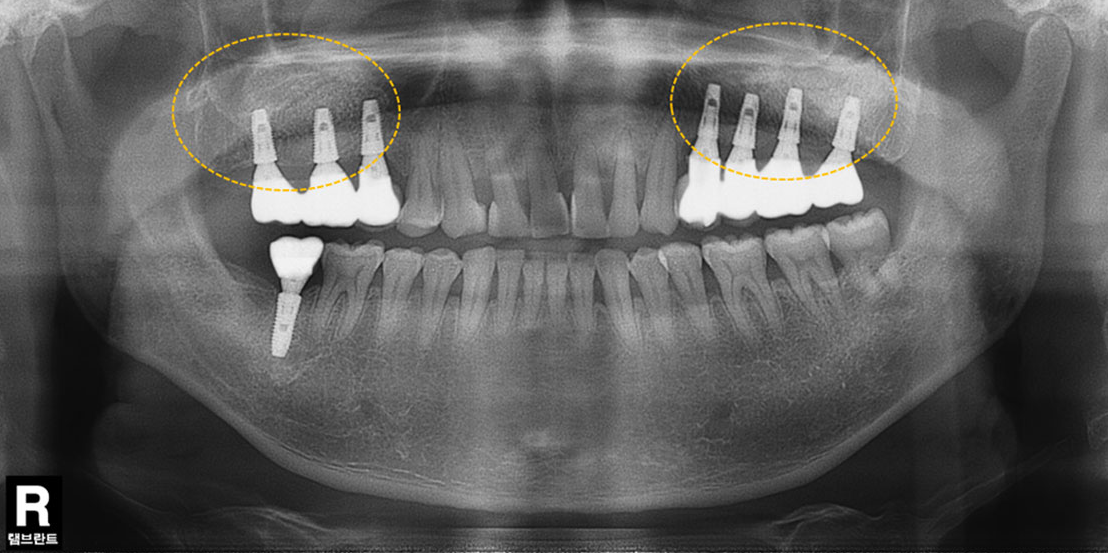

상악동 공간이 내려앉은 경우

윗턱뼈의 두께가 얇은 경우

뼈이식 임플란트 치료 예시

뼈의 소실량이 많은 경우

매복된 제2 대구치

매복된 사랑니

견고한 금속 차폐막 적용